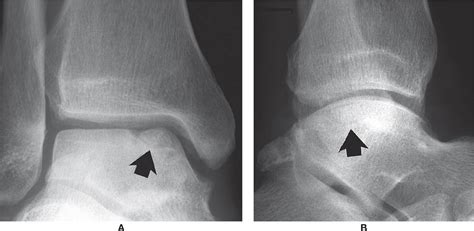

Ankle fracture, malleolar fracture, ankle arthroscopy, arthroscopy assessment the mechanism of injury, patterns of injury and intraarticular chondral injury were documented. In this tutorial i'll show you my favorite updates to the voronoi fracture object in c4d r19. J bone joint surg am. Сибирский научный медицинский журнал, том 36, № 2, 2016. I'll show you how to use connectors, geometry glue. The authors thoroughly review transchondral fractures of the talar dome. Denosumab or bisphosphonate use, particularly alendronate, can be risk factor. Transchondral fractures (osteochondritis dissecans) of the talus. A transchondral fracture is a fracture of the articular surface of a bone, produced by a force transmitted from the articular surface of a contiguous bone across the joint and through the articular. The etiology, treatment and difficulty in diagnosis of transchondral fractures of the talar dome are discussed. Arthroscopic treatment of transchondral talar dome fractures. Accurate reduction and rigid fixation are required to ensure. Diagnosis and treatment of fractures of the talus: The journal of bone and joint surgery. Fractures may be further classified by cause as pathologic, stress, or transchondral. Transchondral fractures (osteochondritis dissecans) of the 4. .nomenclature, including osteochondritis dissecans, talar dome fracture, transchondral fracture, and flake fracture.